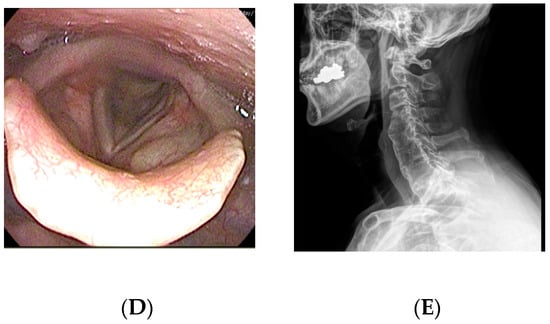

A 65-year-old man visited the department of otolaryngology presenting with dysphagia and odynophagia for 3 months. Although he was able to have an oral diet, he felt severe difficulty in swallowing both solid and liquid food. He complained of a 12-kilogram reduction in body weight due to difficulty swallowing. He had undergone gastrectomy for stomach cancer 13 years ago and was taking psychiatric medications for bipolar disorder. Laryngoscopic examination revealed a protruding mass at the posterior pharyngeal wall obstructing the laryngeal entrance (Figure 2). Lateral cervical radiography and CT revealed a bridging osteophyte at the anterior cervical and thoracic vertebral bodies, suggesting DISH. Preoperative VFSS revealed moderate dysphagia in the oral and pharyngeal phases with incomplete closure of the epiglottis. For solid food, there were large amounts (>50%) of residue at the vallecular pouch and a moderate amount (10–50%) at the pyriform sinus. For liquid, direct aspiration to the trachea was identified. As conservative treatment with a dysphagia diet was not effective, he was referred to the spine center for surgical removal of the osteophyte. The surgery was performed via the modified Smith–Robinson approach and took 50 min with blood loss of less than 50 mL. Bone wax was applied to the bony margin after osteophyte removal. His symptoms markedly improved immediately after the surgery. There was no evidence of regrowth of the osteophyte at 1-year postoperative follow-up.

Figure 2.

A 65-year-old man presented with dysphagia and odynophagia for the past 3 months and 12 kg weight loss. (A) Preoperative laryngoscopy revealed a protruding mass at the posterior pharyngeal wall obstructing the laryngeal entrance. (B) Lateral cervical radiograph showed a bridging osteophyte at the anterior cervical and thoracic vertebral bodies, suggesting DISH. (C) Preoperative visual fluoroscopic swallowing study revealed moderate dysphagia in the oral and pharyngeal phases with incomplete closure of the epiglottis. (D) Postoperative laryngoscopy showed disappearance of the protruding mass at the posterior pharyngeal wall. (E) There was no evidence of regrowth of the osteophyte at 1-year postoperative radiograph.